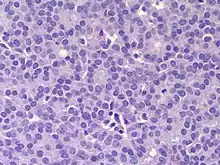

The microscopic histopathology (refer to adjacent high-power photomicrograph) of EPC tissues typically shows papillary structures with fibrovascular cores and proliferating neoplastic epithelial cells growing within cystic spaces, all of which are enclosed within a dense fibrous capsule. In general, EPC tumors do not have areas of neuroendocrine degeneration or myoepithelial cells.[6] The presence of a dense fibrous capsule distinguishes EPC from other papillary breast tumors, particularly PDCIS;[3] the absence of neuroendocrine differentiation areas helps distinguishes EPC from SPC tumors;[3] and the absence of peripherally located myoepithelial cells helps distinguish EPC from PDCIS tumors.[7] EPC tumors may be totally contained within their fibrous capsules or have one or more areas that have invaded through the capsule to normal breast tissues and/or chest muscles; these two variants are termed in situ EPC and infiltrative EPC, respectively.[3][5] In a study of 25 individuals with EPC, 14 had in situ and 11 had invasive disease with 6 of the invasive tumors rated as high grade (see high grade tumors) based on their microscopic histopathology.[5] Rarely, EPC tumors metastasize to nearby sentinel lymph nodes, other nearby axillary lymph nodes, and/or distant tissues; these metastases have in general shown papillary morphologic features similar to their primary tumors.[6] Uncommonly, EPC tumors co-exists with nearby PDCIS,[7] invasive carcinoma of no special type, invasive cribriform carcinoma of the breast, mucinous carcinoma, or tubular carcinoma[3] tumors.